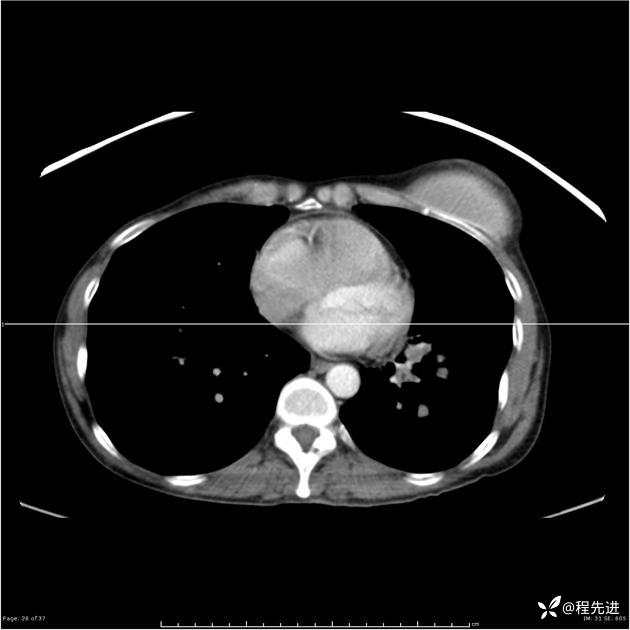

病例女,53岁,气管、左主支气管、下叶支气管内结节,乳头状瘤?期待你的精彩解读

女,53岁

乳头状瘤?